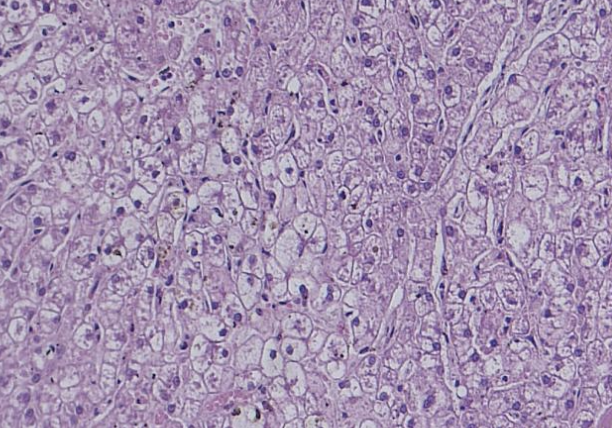

what does the image show?

glycogen type VH

canine steroid induced hepatopathy

hepatocellular glycogen accumulation

what kind of hepatocellular accumulation has Indiscrete intracytoplasmic vacuoles. Can be induced by prolonged treatment with steroids in dogs